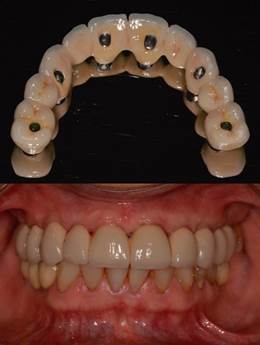

La impresión definitiva se realizó con cubeta individual a nivel de pilares cónicos, con técnica de cubeta abierta y polivinilsiloxano de adición monofásico (EliteHD monophase, Zhermack®). Previamente, todos los pilares de impresión fueron individualizados con técnica indirecta para transferir los perfiles de emergencia y se ferulizaron con resina acrílica autopolimerizable de baja contracción (Pattern Resin LS, GC®) (Figura 5c).

Para la fabricación de la estructura definitiva, se solicita al laboratorio confeccionar una estructura metálica CAD-CAM de arco total en relación a la prótesis provisoria, para lo cual se toman matrices de silicona del contorno del provisorio. Se chequea el asentamiento y ajuste pasivo de la estructura clínica y radiográficamente, se revisan espacios disponibles para la porcelana (Figura 5d). Se solicita al laboratorio la adición de porcelana feldespática de recubrimiento. Posteriormente se prueba estructura final, se chequea oclusión, se realizan ajustes en zona de troneras para dejar espacios higienizables y se envía nuevamente a laboratorio para glaseado. El día de la instalación definitiva se asienta la estructura de forma pasiva y se torquea de manera cruzada. Se da torque definitivo sugerido por el fabricante de 15 Ncm. Se sellan chimeneas, se chequea oclusión y se realiza pulido final (Figura 6). Finalmente, se logra una oclusión funcional y estable, además de un perfil y soporte labial armónicos, al restituir únicamente estructura dentaria (Figura 7).